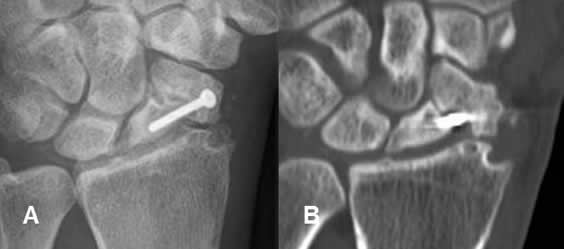

Fig 124. Seudoartrosis del escafoides.

A: Rx AP y B: TAC reconstrucción coronal. Seudoartrosis del escafoides, manejada con tornillo.

Fig 125. Seudoartrosis.

A: Rx AP y B: TAC reconstrucción sagital. Fractura con extremos escleróticos y con poca formación de callo óseo, por seudoartrosis.